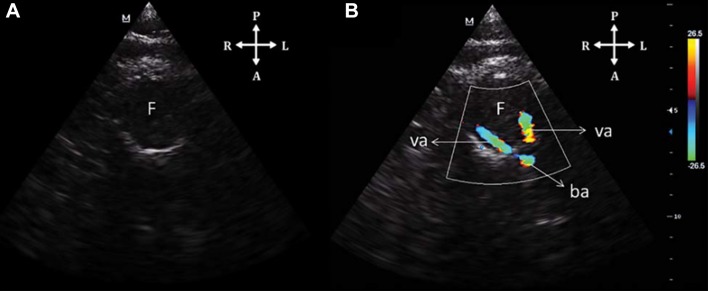

In the transforaminal window, a central hypoechoic structure is recognized, corresponding to the foramen magnum; color Doppler shows an inverted “v” normally coded blue, corresponding to the intracranial segment of the vertebral arteries and the basilar artery (Fig. 12).

Fig. 12.

TCCS from a transforaminal view. a Two-dimensional imaging. F hypoechoic foramen magnum, b Color Doppler showing the V-shaped artery configuration of posterior cerebral circulation. va vertebral arteries, ba basilar artery, F foramen magnum

(Reproduced with permission from [25])